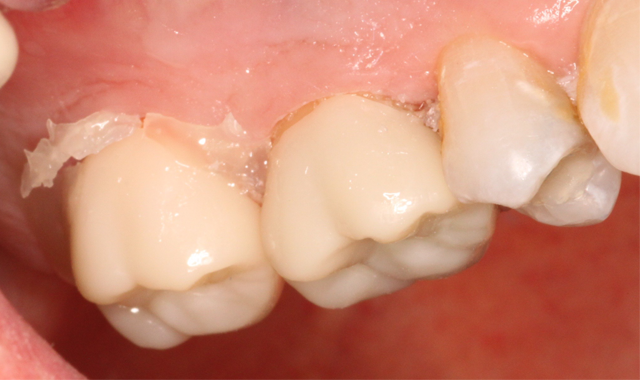

Both zirconia crowns were fully seated and occlusion was confirmed. A three-second tack cure followed at the buccal and lingual margins. (Fig. 6) Excess cement was removed and the margins were once again light cured for 20 seconds each.

Again, both restorations were secured during this process. Keep in mind that 90 percent of bond strength in most of these cements occurs within the first 10 minutes, so it is critical to make sure when the restoration is seated, it is secured. Disturbing those early bonds could be detrimental. The final view of the restored maxillary molars is shown in Figures 7 and 8.

Fig. 7 Fig. 8